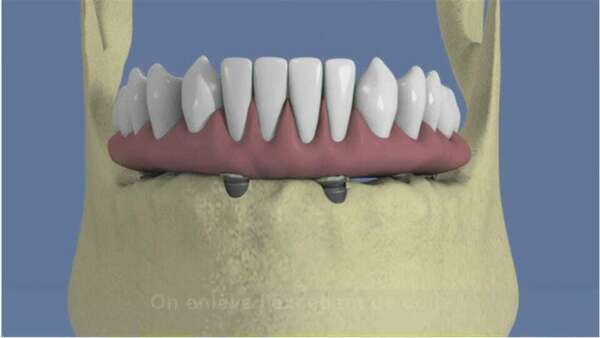

Pour les édentés complets mandibulaires, 4 implants sont répartis sur la mâchoire dans lesquels le bridge est ensuite transvissé